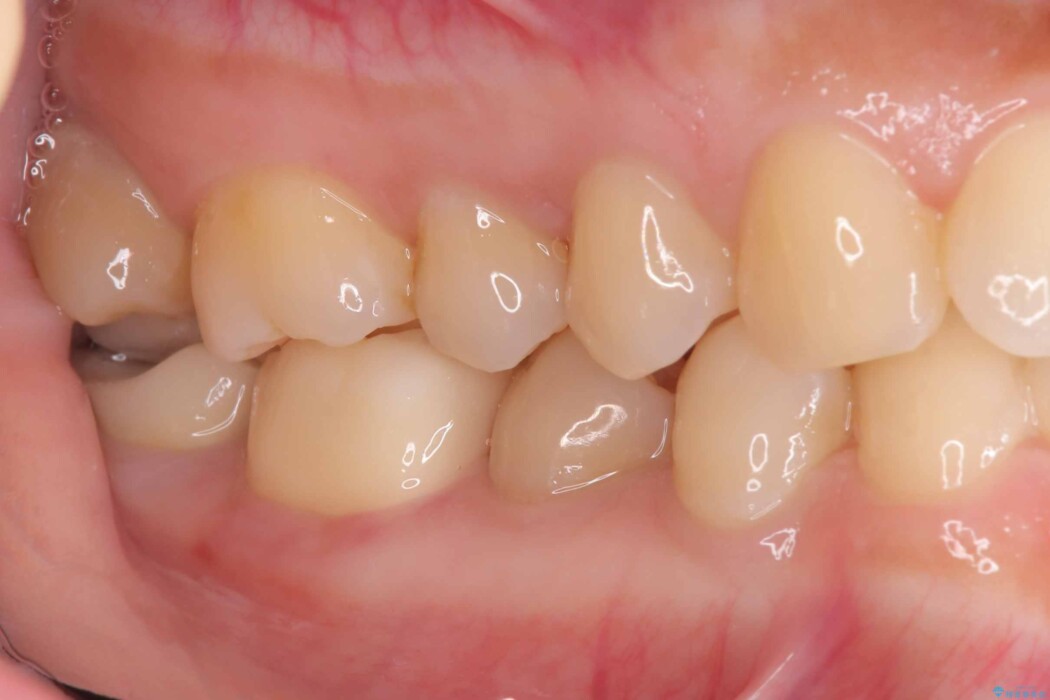

除去後は、再発リスクを抑え長期的な安定を図るために、適合精度が高く劣化しにくいセラミックインレーによる修復を計画しました。